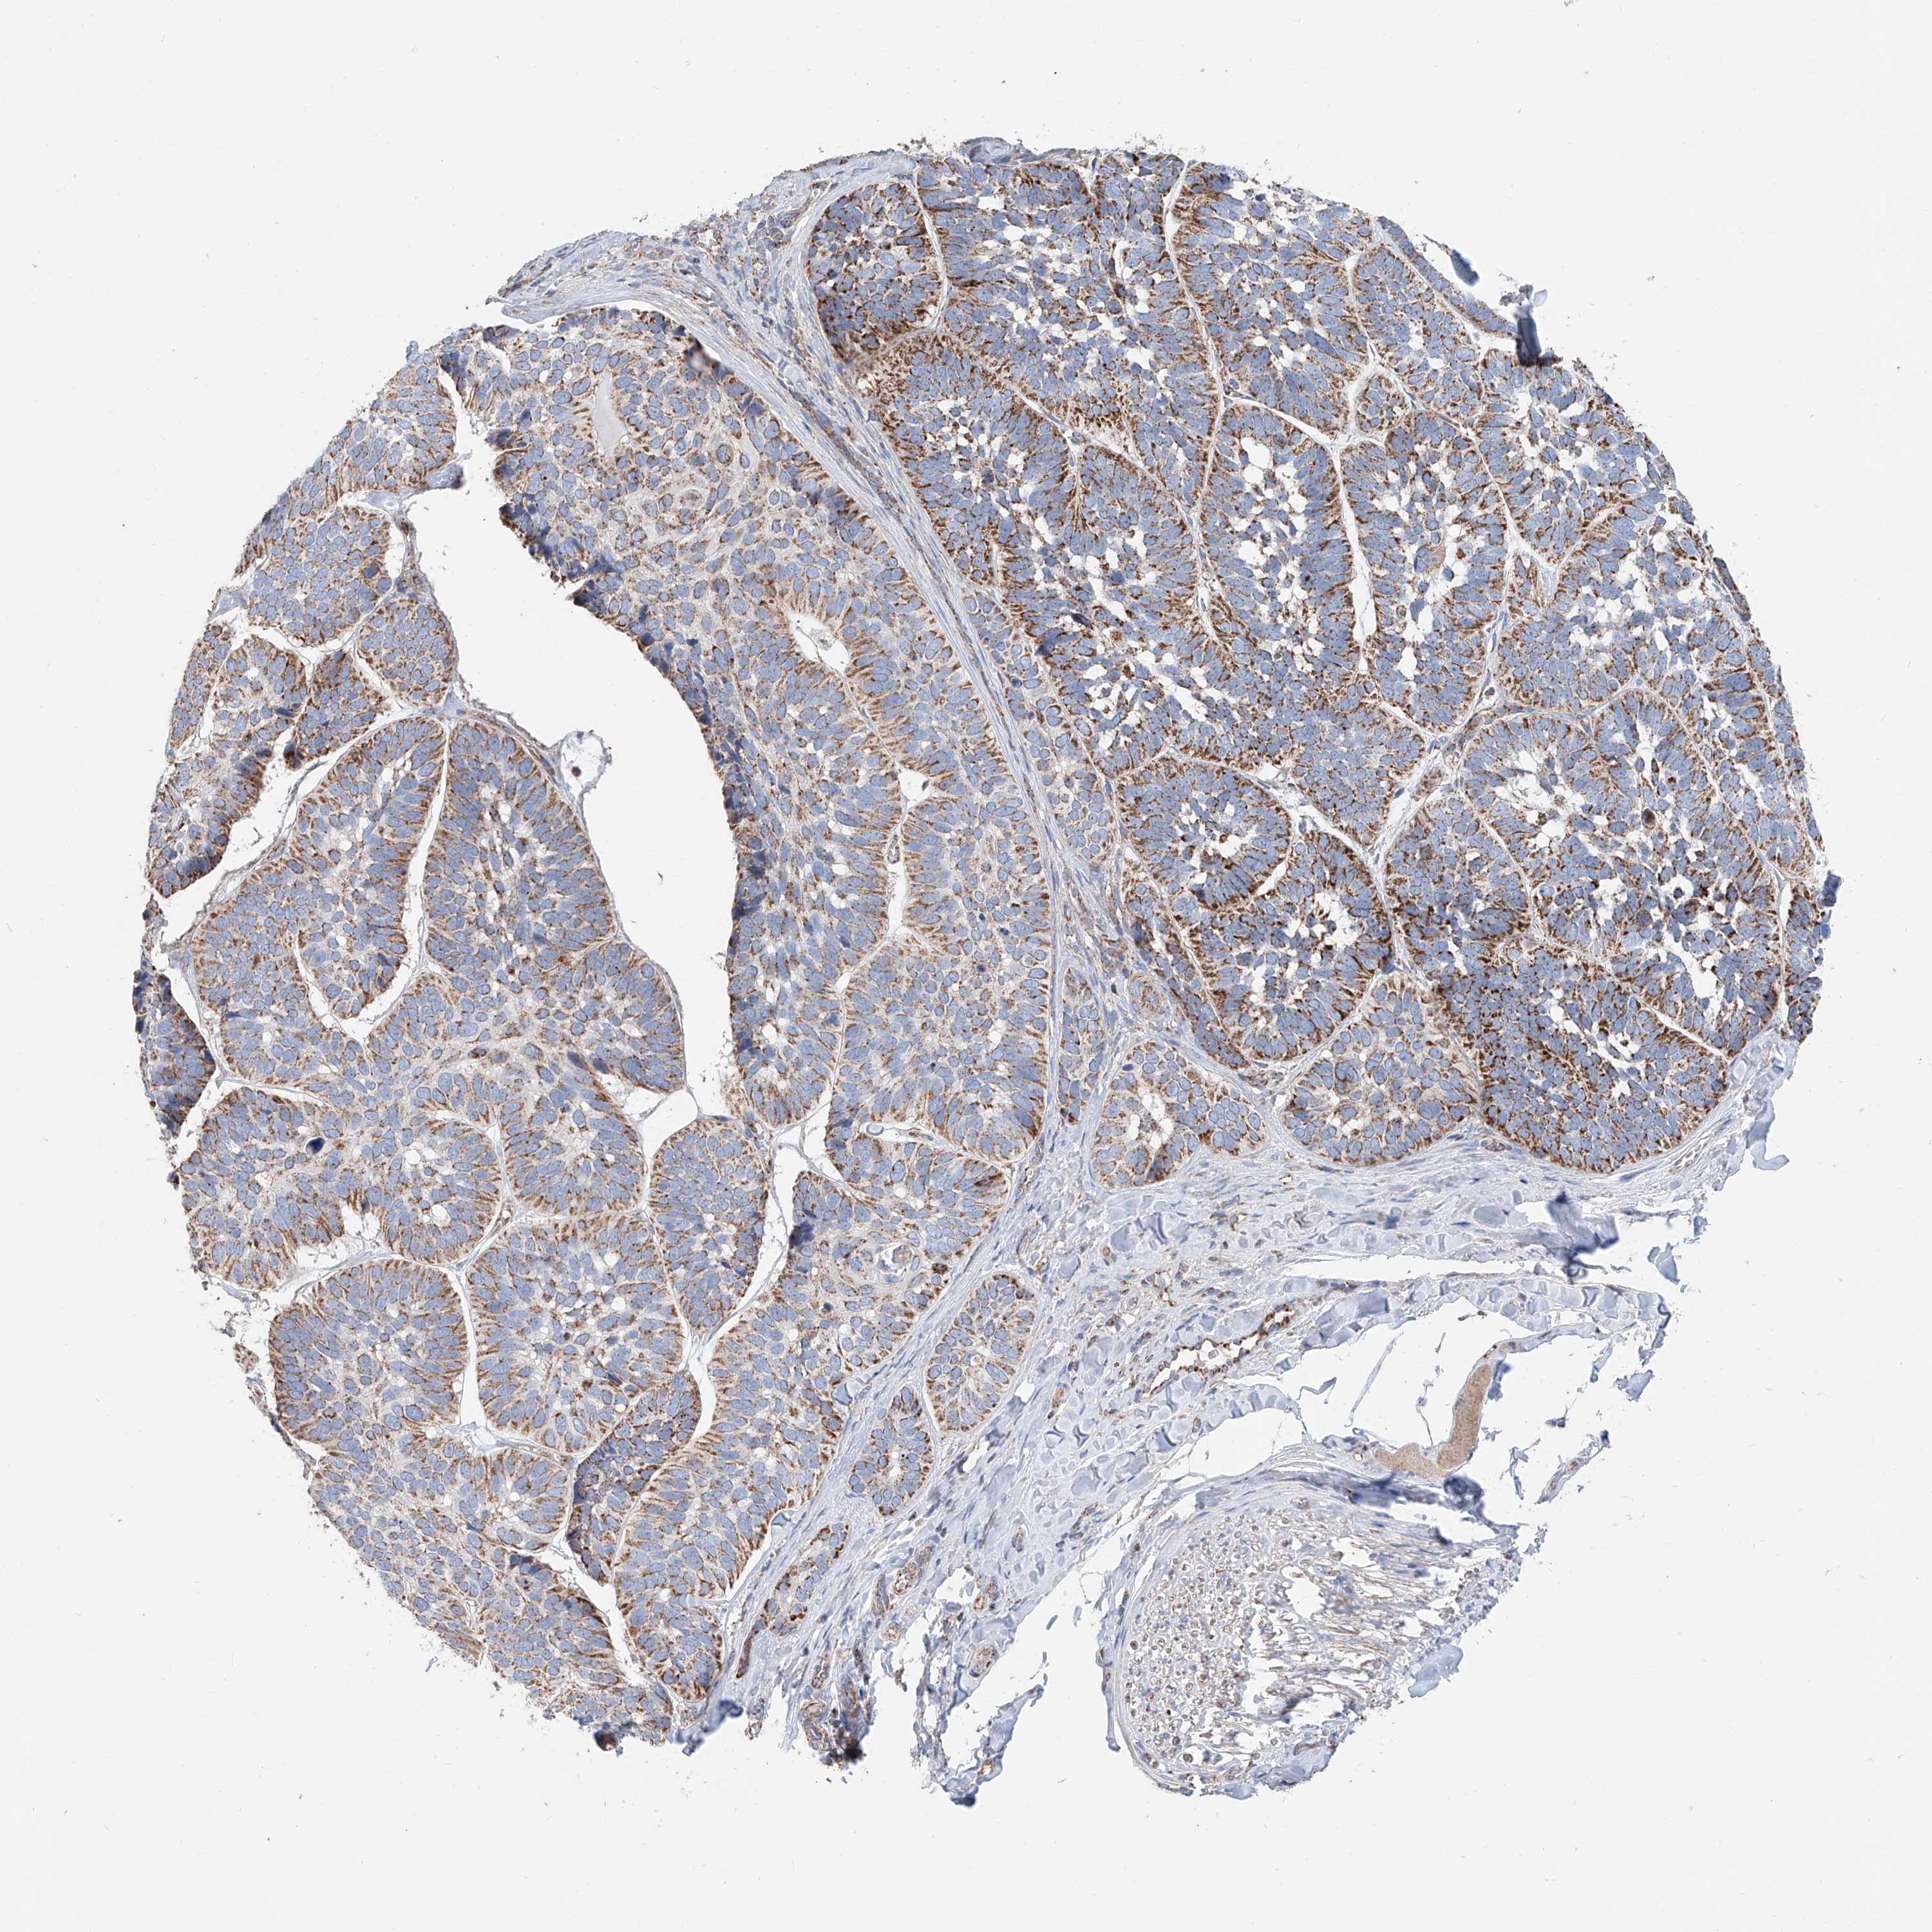

SKIN CANCER - Protein expressioni

A mouse-over function shows sample information and annotation data. Click on an image to view it in a full screen mode. Samples can be filtered based on level of antibody staining by selecting one or several of the following categories: high, medium, low and not detected. The assay and annotation is described here.

Antibody stainingi

Antibody staining in the annotated cell types in the current human tissue is reported as not detected, low, medium, or high, based on conventional immunohistochemistry profiling in selected tissues. This score is based on the combination of the staining intensity and fraction of stained cells.

Each image is clickable and will lead to virtual microscopy that enables deeper exploration of all samples and also displays staining intensity scores, fraction scores and subcellular localization as well as patient and tissue information for each sample.

Antibody CAB002781

Antibody CAB068195

Staining

High

Medium

Low

Not detected

Intensity

Strong

Moderate

Weak

Negative

Quantity

>75%

75%-25%

<25%

None

Location

Nuclear

Cytoplasmic/membranous

Cytoplasmic/membranous,nuclear

Squamous cell carcinoma, NOS

Squamous cell carcinoma, metastatic, NOS

Basal cell carcinoma

Papilloma, NOS